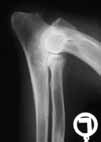

| Zugelassene

Röntgenstelle für HD

(Hüftgelenksdysplasie), ED

(Ellenbogengelenksdysplaie) und OCD

(Osteochondrosis dissecans). |